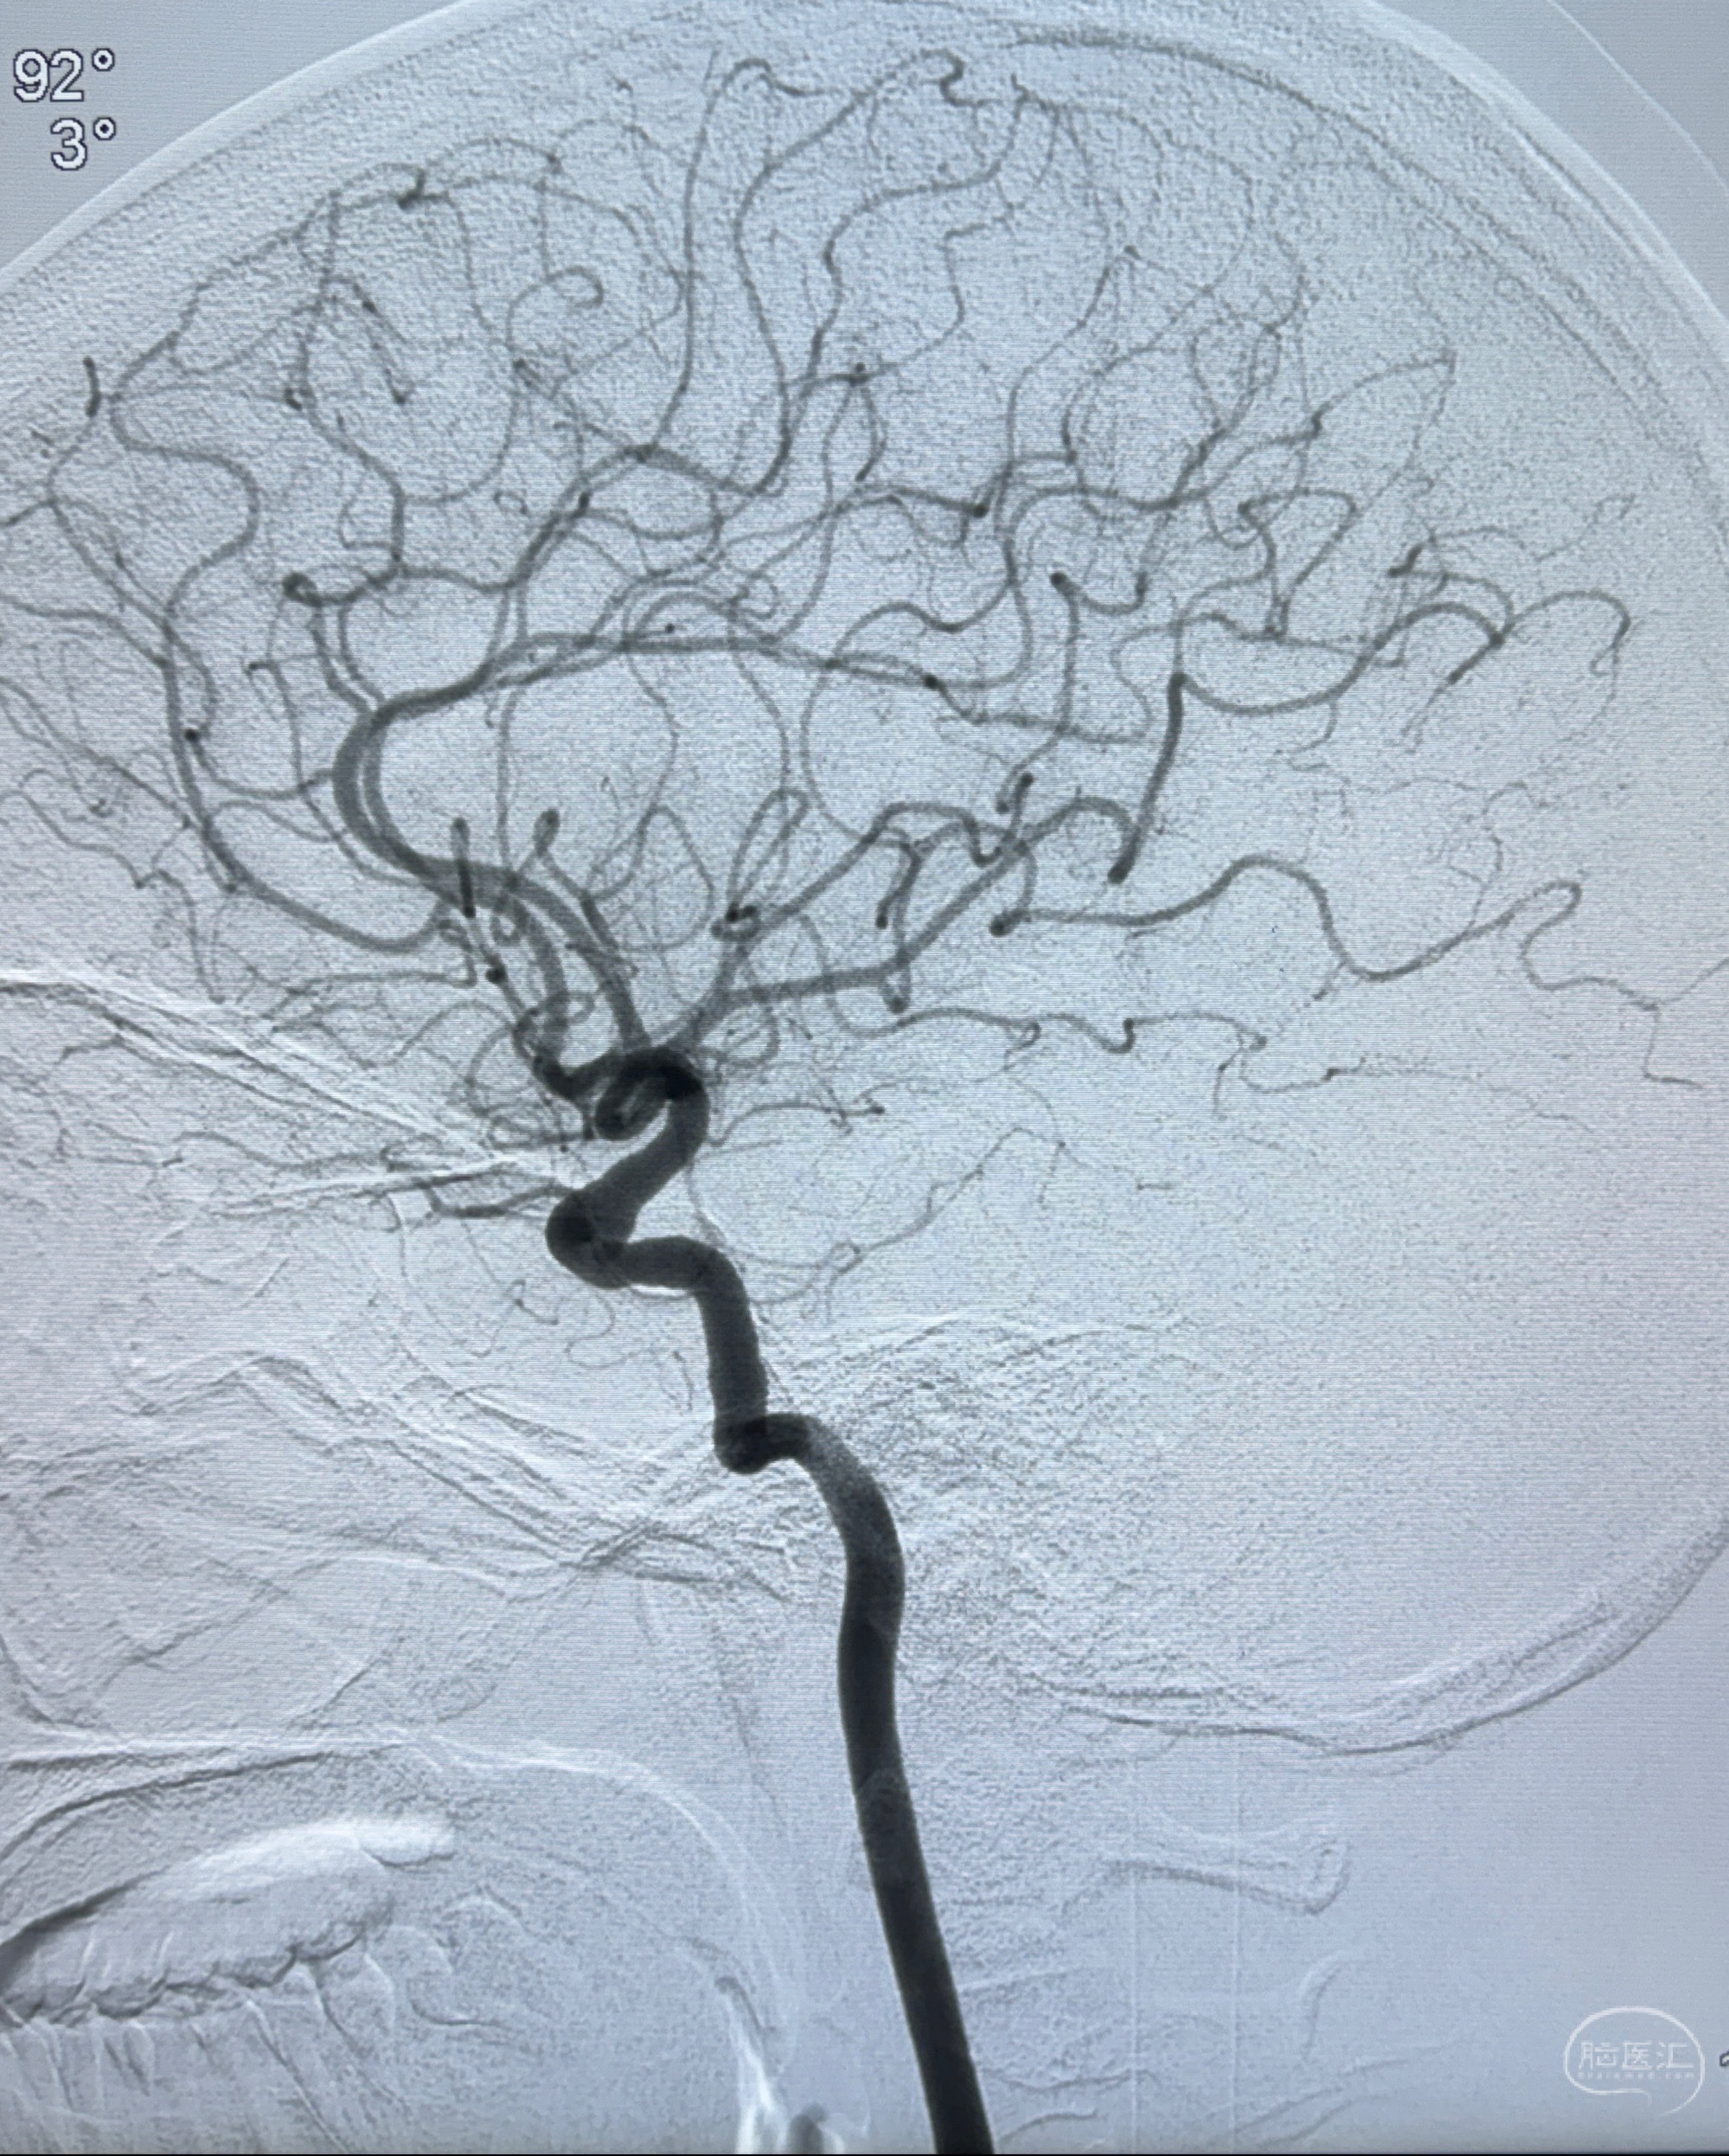

2023-11-13DSA:左侧颈内动脉眼动脉后壁动脉瘤

2023-11-29全麻下行NeuroformEZ4.5-20mm支架辅助栓塞